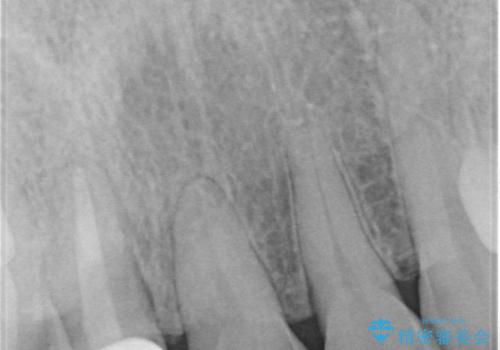

10年前に根管治療を他院で行っており、根尖性歯周炎の予防のため根管治療から行いました。被せものはオールセラミッククラウンで治療を行いました。

10年前にラバーダムシート無しに根管治療を行っており、現在、症状は出ていませんが、根尖性歯周炎の予防のため根管治療から行いました。ホームホワイトニングを2週間行って頂き、その後、オールセラミッククラウンで治療を行っています。

※根尖性歯周炎は根管内の細菌が原因となり発症します。唾液の中には数千億個もの細菌が存在します。したがって、ラバーダムシートを使用し、歯を唾液から守ってあげることが大切になります。当院では、ラバーダムシートの使用に加え、マイクロスコープ(歯科用顕微鏡)、P-MAX(超音波洗浄の機械)を使用して治療を行っています。

※被せものでは歯と被せものの適合がとても大切になります。適合が悪い被せもの(歯と被せものの間に隙間がある)を入れるとそこに汚れが溜り虫歯の原因となります。当院では精度が高い被せものを追求するため、サージテル(拡大鏡)や型取りの材料にシリコン材を使用しています。